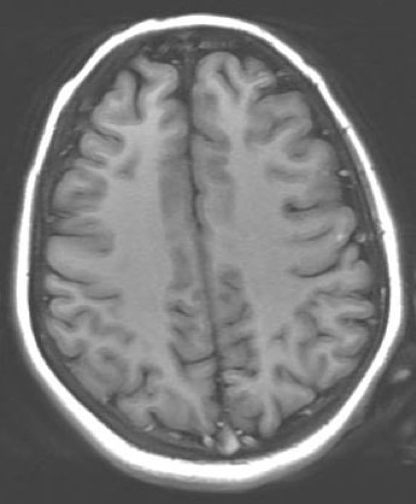

Magnetic resonance imaging scans of the brain were obtained on day 10 of hospitalization. The results demonstrated mild smooth dural enhancement after LP, without evidence of acute infarct, hemorrhage, mass, or hydrocephalus (Figure 1).

Figure 1. Magnetic resonance imaging scans of the brain with contrast (left) and without contrast (right), obtained on hospital day 10, showed mild smooth dural enhancement after LP. No evidence of acute infarct, hemorrhage, mass, or hydrocephalus was present.